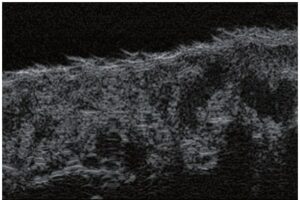

Die Doppler-Sonographie ermöglicht die Darstellung großer Gefäße und Perforatoren, die sich meist in tieferen Bereichen des subkutanen Gewebes befinden. Mit klassischem Ultraschall lassen sich kleinere Gefäße jedoch nicht darstellen. Für die Darstellung kleinerer Gefäße, die oberflächlich unter der Epidermis und im oberen subkutanen Gewebe liegen, wird HFU eingesetzt. Mit Sonden über 20 MHz Frequenz erhält man hochauflösende Ultraschallbilder, auf denen Objekte kleiner als 0,1 mm unterscheidbar sind. Mit zunehmender Auflösung nimmt jedoch die Eindringtiefe ab. Je nach Sonde und Gerät beträgt die maximale Eindringtiefe etwa 20–30 mm. Diese Eindringtiefe bei gleichzeitig hoher Bildauflösung ermöglicht die Beurteilung sehr kleiner Gefäße. HFU erlaubt die genaue Bestimmung des Verlaufs und der Lage kleiner Gefäße in der Haut, was entscheidend für die Wahl der Verschlussmethode und die Planung des Eingriffs ist. Oft sind an der Hautoberfläche nur wenige Gefäße sichtbar – erst durch die Ultraschalluntersuchung lässt sich die tatsächliche Anzahl und der Verlauf feststellen. Für einen erfolgreichen Verschluss muss das gesamte Gefäß behandelt werden, nicht nur der sichtbare Teil, da sonst eine schnelle Rekanalisation erfolgt (7). Häufig ändert das an der Haut sichtbare Gefäß seinen Verlauf, wird gewundener und zieht in tiefere Hautschichten (8). HFU ermöglicht zudem die Darstellung der Perforatoren zwischen kleinen Gefäßen und die Messung grundlegender Parameter wie Durchmesser, Wandstärke, Tiefe und Blutfluss (6). Mit der 40-MHz-Sonde von Ultrasonix kann auch der Blutfluss mittels Farbdoppler visualisiert werden.